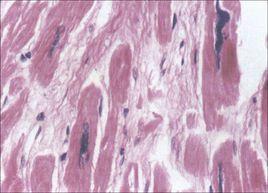

任何原因只要能引起組織細胞損傷,均可導致組織細胞發生變性、壞死和炎症反應,如果損傷很小,損傷細胞周邊正常實質細胞將發生增生修復,這種修復可完全恢復正常的結構和功能。然而如果損傷較大或反覆損傷超出了損傷周圍實質細胞的再生能力時,間質纖維結締組織(細胞外基質)將大量增生對缺損組織進行修復,即發生纖維化的病理改變。因此本質上纖維化是組織遭受損傷後的修復反應,以保護組織器官的相對完整性。增生的纖維結締組織雖然修復了缺損,但卻不具備原來器官實質細胞的結構和功能。如果這種修復反應過度、過強和失控時,就會引起器官的纖維化和導致器官的功能下降。

由此可見,纖維化是指由於炎症導致器官實質細胞發生壞死,組織內細胞外基質異常增多和過度沉積的病理過程。輕者成為纖維化,重者引起組織結構破壞而發生器官硬化。

1概述:纖維化(fibrosis)可發生於多種器官,主要病理改變為器官組織內纖維結締組織增多,實質細胞減少,持續進展可致器官結構破壞和功能減退,乃至衰竭,嚴重威脅人類健康和生命。